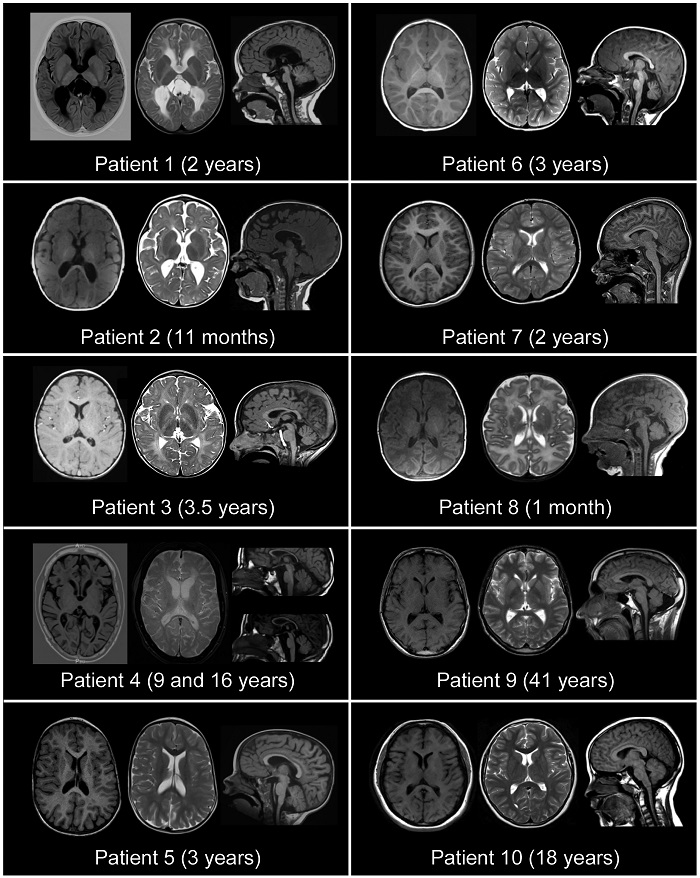

Los resultados, publicados en la revista Brain, aseguran que se han identificado mutaciones de este gen en 10 familias y las pruebas bioquímicas realizadas en el laboratorio han confirmado que estas variantes serían las responsables de los síntomas.

El estudio ha diagnosticado 10 pacientes afectados de esta nueva enfermedad y ha encontrado el gen responsable mediante la secuenciación de su genoma.

De estos casos, cuatro eran españoles -dos niños y dos adultos- y los otros eran tratados en centros internacionales como el Broad Institute de Boston o el National Human Genome Research Institute de Bethesda, ambos en EU, y los síntomas abarcaban desde el retraso global en el neurodesarrollo y el déficit intelectual, a menudo con crisis epilépticas, hasta una simple cojera.